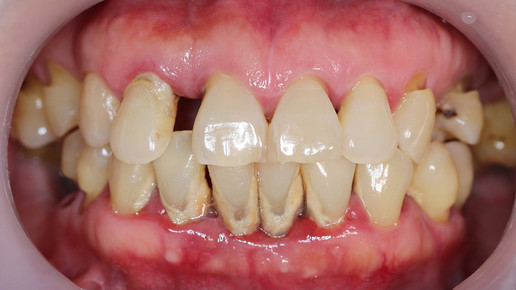

Diabetiker:innen haben ein dreimal höheres Risiko für eine Zahnfleischerkrankung als Gesunde. Betroffene können Zahnfleischentzündungen, Abzesse und Risse in den Mundwinkeln erleiden. Diese Symptome können zudem ein Hinweis auf einen unentdeckten Diabetes sein. Etwa ein Drittel aller Patient:innen wissen nichts von ihrer Erkrankung.

Ist die Insulinsekretion gestört, oder bereits eine Insulinresistenz bei den Zellen eingetreten, ist der Blutzuckerspiegel dauerhaft erhöht. Das führt wiederum zu einer höheren Anfälligkeit für Zahnfleischentzündungen. Das Immunsystem reagiert intensiver auf Zellgifte von Plaque-Bakterien am Zahnfleischrand. Veränderungen in den Gefäßwänden und Durchblutungsstörungen als Folge des Diabetes, erschweren es dem Körper zusätzlich, die Entzündungsprozesse zu kontrollieren. Liegt eine Parodontitis vor, so führt die Entzündung insgesamt dazu, dass Insulin noch schlechter wirken kann und der Diabetes sich verschlimmert. Es entsteht ein Teufelskreis, in dem sich beide Erkrankungen gegenseitig verstärken und das Risiko für weitere Folgeerkrankungen erhöht wird.

Deshalb ist es wichtig, eine effektive Parodontitis-Therapie durchzuführen und somit auch die Einstellung des Blutzuckerspiegels bei Typ-2-Diabetiker:innen zu verbessern. Eine gute Mundhygiene ist dabei Grundlage der Behandlung und unerlässlich. Da Parodontitis eine chronische Erkrankung ist, kann man sie nur stoppen, aber nicht gänzlich heilen. Mit der richtigen Behandlung kann ein Fortschreiten und der damit verbundene Zahnverlust verhindert werden – allerdings bedeutet das „lebenslänglich“. Betroffene sollten möglichst auf sehr kalte oder heiße und süße Speisen verzichten, da diese die offen liegenden Zahnhälse reizen. Durch die gelockerten Zähne können viele Patient:innen auch keine harten, zähen oder klebrigen Lebensmittel mehr genießen. Nach dem gründlichen Zähneputzen empfiehlt es sich, eine alkoholfreie Mundspülung zu benutzen. Die tägliche Reinigung der Zahnzwischenräume mit Zahnseide und Zahnzwischenraumbürstchen sollte in die Reinigungsroutine eingegliedert werden, um das Fortschreiten der Parodontitis zu vermeiden.